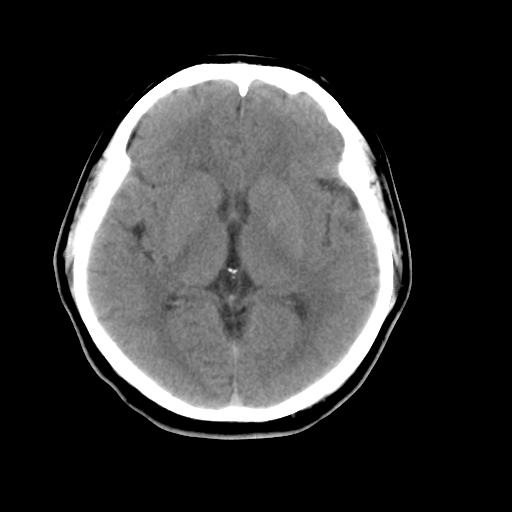

以下是引用liuyue在2008-4-28 13:34:00的发言:[br]右额叶条状高密度影,边缘清楚,周围未见水肿及占位.[br]考虑:血管畸形可能性大.[br]建议:强化ct扫描或mri检查.除外脑回钙化.

以下是引用论黑辩白在2008-4-28 12:53:00的发言:[br]右额叶局限性脑萎缩,右额叶见条状高密度影,建议mri进一步检查。[br][br][本贴已被 论黑辩白 于 2008-4-28 13:08:16 修改过]